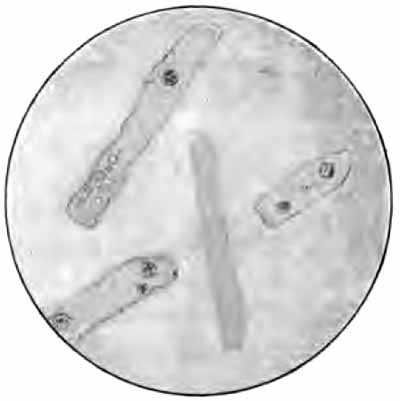

Curschmann's spirals

FIG. 5.—Curschmann's spirals: I., Natural size; II. and III., enlarged: a, central fiber (after Curschmann).

2. Curschmann's Spirals.—These peculiar structures are found most frequently in bronchial asthma, of which they are fairly characteristic. They may occasionally be met with in chronic bronchitis and other conditions. Their nature has not been definitely determined.

Macroscopically, they are whitish or yellow, twisted threads, frequently coiled into little balls (Fig. 5, I.). Their length is rarely over half an inch, though it sometimes exceeds two inches. Under a two-thirds objective they appear as mucous threads having a clear central fiber, about which are wound many fine fibrils (Fig. 5, II. and III.). Leukocytes are usually present within them, and sometimes Charcot-Leyden crystals. The central fiber is not always present.